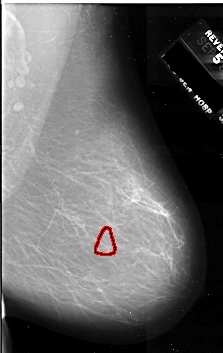

A_1075_1.RIGHT_CC

RIGHT_CC LINES 6271 PIXELS_PER_LINE 4081 BITS_PER_PIXEL 16 RESOLUTION 42 OVERLAY

FILE: A_1075_1.RIGHT_CC.OVERLAY

TOTAL_ABNORMALITIES 1

ABNORMALITY 1

LESION_TYPE CALCIFICATION TYPE PLEOMORPHIC DISTRIBUTION CLUSTERED

ASSESSMENT 4

SUBTLETY 2

PATHOLOGY MALIGNANT

TOTAL_OUTLINES 1

BOUNDARY